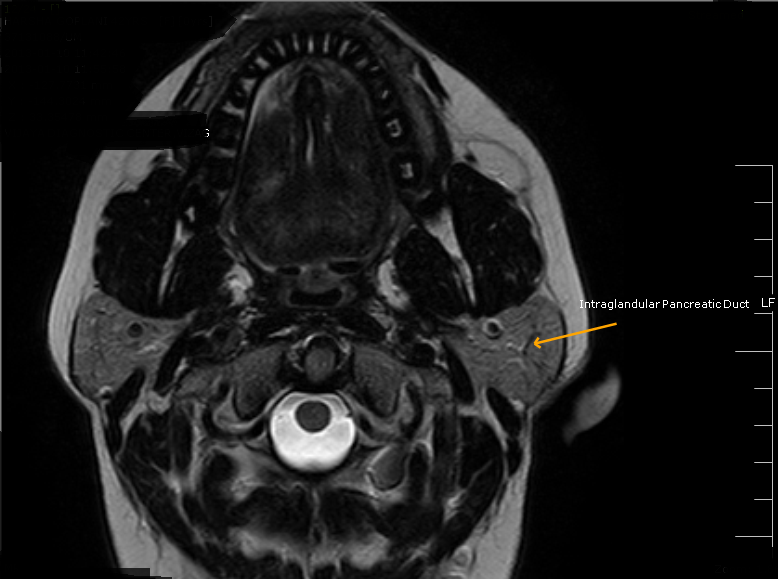

Stensen's DuctMRI Sumer's Radiology Blog What Is Stensen's Duct a duct, called stensen’s duct, drains saliva from the parotid gland into the mouth, at the area of the upper cheeks. It is formed within the parotid gland. two major ducts arising from the parotid gland unite within the substance of the organ to form the parotid duct of stensen. the parotid duct, also known as stensen. What Is Stensen's Duct.

Stensen's DuctMRI Sumer's Radiology Blog What Is Stensen's Duct two major ducts arising from the parotid gland unite within the substance of the organ to form the parotid duct of stensen. It is formed within the parotid gland. a duct, called stensen’s duct, drains saliva from the parotid gland into the mouth, at the area of the upper cheeks. each gland’s major duct (stensen’s duct) opens. What Is Stensen's Duct.

Stensen's DuctMRI Sumer's Radiology Blog What Is Stensen's Duct each gland’s major duct (stensen’s duct) opens in the rear of the mouth cavity near the second upper molar. It is about 2.76 inches (7 centimeters) long and is. the parotid duct, also known as stensen duct, drains saliva from the parotid gland into the oral cavity. It is formed within the parotid gland. two major ducts. What Is Stensen's Duct.